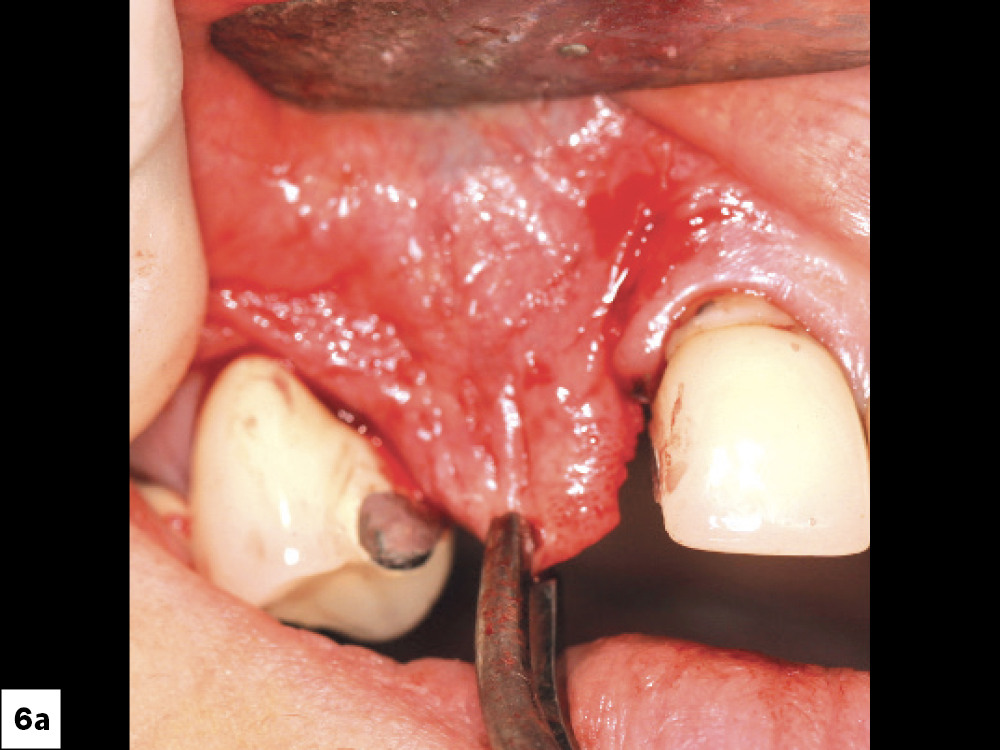

When this wound breakdown occurs, an increased morbidity for dental implant surgery and bone grafting may result because of bacterial contamination (Figs. 1a, 1b). In this article, various techniques and protocols will be discussed to prevent ILO and manage this complication.

Incision line opening: (a) implants, (b) guided bone regeneration procedures.

Figures 1a, 1b: Incision line opening: (a) implants, (b) guided bone regeneration procedures.